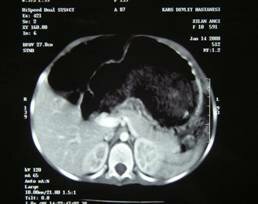

Case Report: Spontaneous Liver Hydatid Cyst Rupture in a Child

A Sumer, MD, K Caglayan, MD, E Altinli, MD, N Koksal , MD

A Diagnostic Approach to Penetrating Diaphragmatic Rupture via M-Mode Ultrasonography

M Emet, MD, S Aslan, MD, O Onbas, MD, Z Cakir, MD, M Uzkeser, MD, G Ozturk, MD, T Ocak, MD